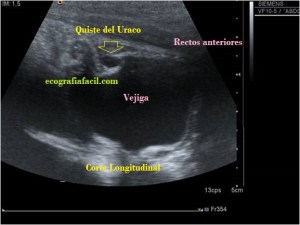

Bien, hemos visto una lesión que es un quiste hidatídico calcificado, pero te preguntarás, si nunca viste uno, ¿cómo es uno cuando tiene «hijas»?, es decir, cuando está activo…Mira este corte transversal de un hígado:

La LOE es de aspecto redondeado, heterogéneo, con multitud de pequeñas imágenes anecoicas e hipoecogénicas, de diferentes tamaños. Esta lesión fue estudiada también mediante otra técnica de imagen, la RMN donde se observa una imagen hiperdensa, con una amalgama de lesiones bordeando a periferia de la misma, de distintos tamaños como se objetiva en la imagen del mismo paciente, de la ecografía inmediatamente superior (Imagen 7). La lesión es activa, por tanto debió de ser tratada, la patología es potencialmente mortal en caso de que el quiste se rompiese.